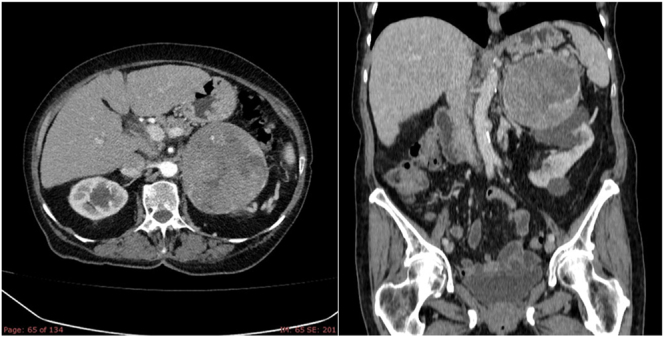

Adrenocortical carcinoma (ACC) is a rare endocrine malignancy with an estimated incidence of 0.7-2 cases per million/year. The rarity of this disease, coupled with limited preclinical models and clinical trials, has hindered progress, resulting in poor outcomes, with a 5-year survival rate of approximately 35%. Currently, the only available curative treatment is complete surgical resection of the adrenal tumor. For unresectable or metastatic ACC, the current standard therapeutic modalities are mitotane, chemotherapy, radiotherapy and locoregional treatments; however, these are noncurative. Mitotane has an adrenolytic and anti-steroidogenic effect, and it is used in the adjuvant setting for high-risk patients, as systemic therapy for metastatic disease, and/or to control hormonal secretion. While key pathways in ACC pathogenesis have been identified as potential therapeutic targets, results with targeted therapies remain modest, showing that there is a clinical unmet need for novel treatments or new combinations of exiting drugs. Effective management requires a multidisciplinary team of experts to optimize outcomes for patients. This article presents a multidisciplinary consensus on the diagnosis, management, prognosis and follow-up of patients with ACC, and the approach to two special contexts, ACC in pregnant women and hormone-producing ACC. The consensus was coordinated by the Spanish Society of Endocrinology and Nutrition (SEEN) and the Spanish Group of Neuroendocrine and Endocrine Tumors (GETNE), with contribution from experts from related societies including the Spanish Association of Surgeons (AEC), Spanish Society of Urology (AEU), Anatomic-Pathology (SEAP), Nuclear Medicine (SEMNIM), Medical Oncology (SEOM) and Radiotherapeutic Oncology (SEOR).